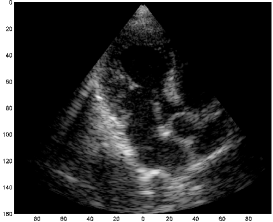

Applied to a single receiver element, the Xampling scheme proposed in [12] achieves good signal reconstruction for an actual ultrasound signal, reflected from a setup of phantom targets. In principle, we could apply this approach to each receiver element individually, resulting in a parametric representation for each of the signals . Being able to digitally reconstruct the detected signals, we could then proceed with the standard beamforming process, outlined in Section II, aimed at constructing the corresponding scanline. Computational effort would have been reduced, by limiting the beamforming process to the support of the estimated pulses. In fact, we could possibly bypass the beamforming stage, by deriving a geometric model which maps the set of delays, , associated with the th reflector, to its two-dimensional position . However, applying the proposed FRI Xampling scheme to signals reflected from biological tissues, we face two fundamental obstacles: low SNR and proper interpretation of the estimated signal parameters, considering the profile of the transmitted beam. These two difficulties may be better understood by examining Fig. 2, which depicts traces acquired for cardiac images of a healthy consenting volunteer using a GE breadboard ultrasonic scanner.

(a)

(b)

In the left plot (a), are signals detected by 32 of 64 active array elements, following the transmission of a single pulse. The pulse was conducted along a narrow beam, forming an arbitrary angle with the axis. The right plot (b) depicts the signal obtained by applying beamforming to the detected signals, as outlined in Section II. Examining the individual traces, one notices the appearance of strong pulses, possibly overlapping, characterized by a typical shape, as proposed in (5). Let us assume that we could indeed extract the delays and amplitudes of these pulses, by applying the proposed FRI Xampling scheme to each element. We suggested that beamforming could be bypassed, by deriving a geometric model for estimating the two-dimensional position of a scattering element, based on the delays of pulses associated with it, yet estimated in different receivers. In order to apply such a model, we must first be able to match corresponding pulses across the detected signals. However, referring to the practical case depicted in (a), we notice that such a task is not at all trivial - the individual signals depict reflections, originating from the entire sector, radiated by the transmitted pulse. These reflections may, therefore, vary significantly across traces. In fact, some pulses, visible in several traces, are not at all apparent in other traces. In contrast, the beamformed signal, by its construction, depicts intensity of reflections originating from along the central transmission axis, while attenuating reflections originating off this axis.

Attempting to apply FRI Xampling to each receiver element individually, we encounter an even more fundamental obstacle, at the earlier stage of extracting the signal’s parametric representation from its low-rate samples. The individual traces contain high levels of noise. The noisy components, especially noticeable in traces 54 and 64, rise mainly from constructive and destructive interference of acoustic waves, reflected by dense, sub-wavelength scatterers in the tissue. The latter are typically manifested as granular texture in the ultrasound image, called speckle, after a similar effect in laser optics [2]. The noisy components inherently induce erroneous results, when attempting to sample and reconstruct the FRI components using the Xampling approach. In extreme scenarios, where the noise masks the FRI component, the extracted parameters will be meaningless, such that any attempt to cope with errors in the parametric domain will turn out useless.

A necessary condition for implementing our approach is that , generated from satisfying (5), is also FRI of similar form. Examining Fig. 2 we notice that exhibits a structure similar to that of the individual signals, comprising strong pulses of typical shape, which may overlap. In this case, there are several obvious advantages in Xampling . First, since are averaged in (after appropriate distortion, derived from the acoustic reciprocity theorem) it naturally exhibits enhanced SNR with respect to the individual signals. The attenuation of noise in the beamformed signal, compared to the individual signals, is apparent in Fig. 2, especially in the interval . Second, is directly related to an individual scanline. This means that we are no longer bothered with the ambiguous problem of matching pulses across signals detected in different elements. Finally, recall that the signal model derived in (5) assumes isolated point-reflectors. Such a model is better justified with respect to since, by narrowing the effective width of the imaging beam, we may indeed approximate its intersection with reflecting structures to be point-like. This effect is noticeable in Fig. 2 where some pulses, visible in individual traces, appear attenuated in the beamformed signal. Such pulses correspond to reflectors located off the central axis of the transmission beam.